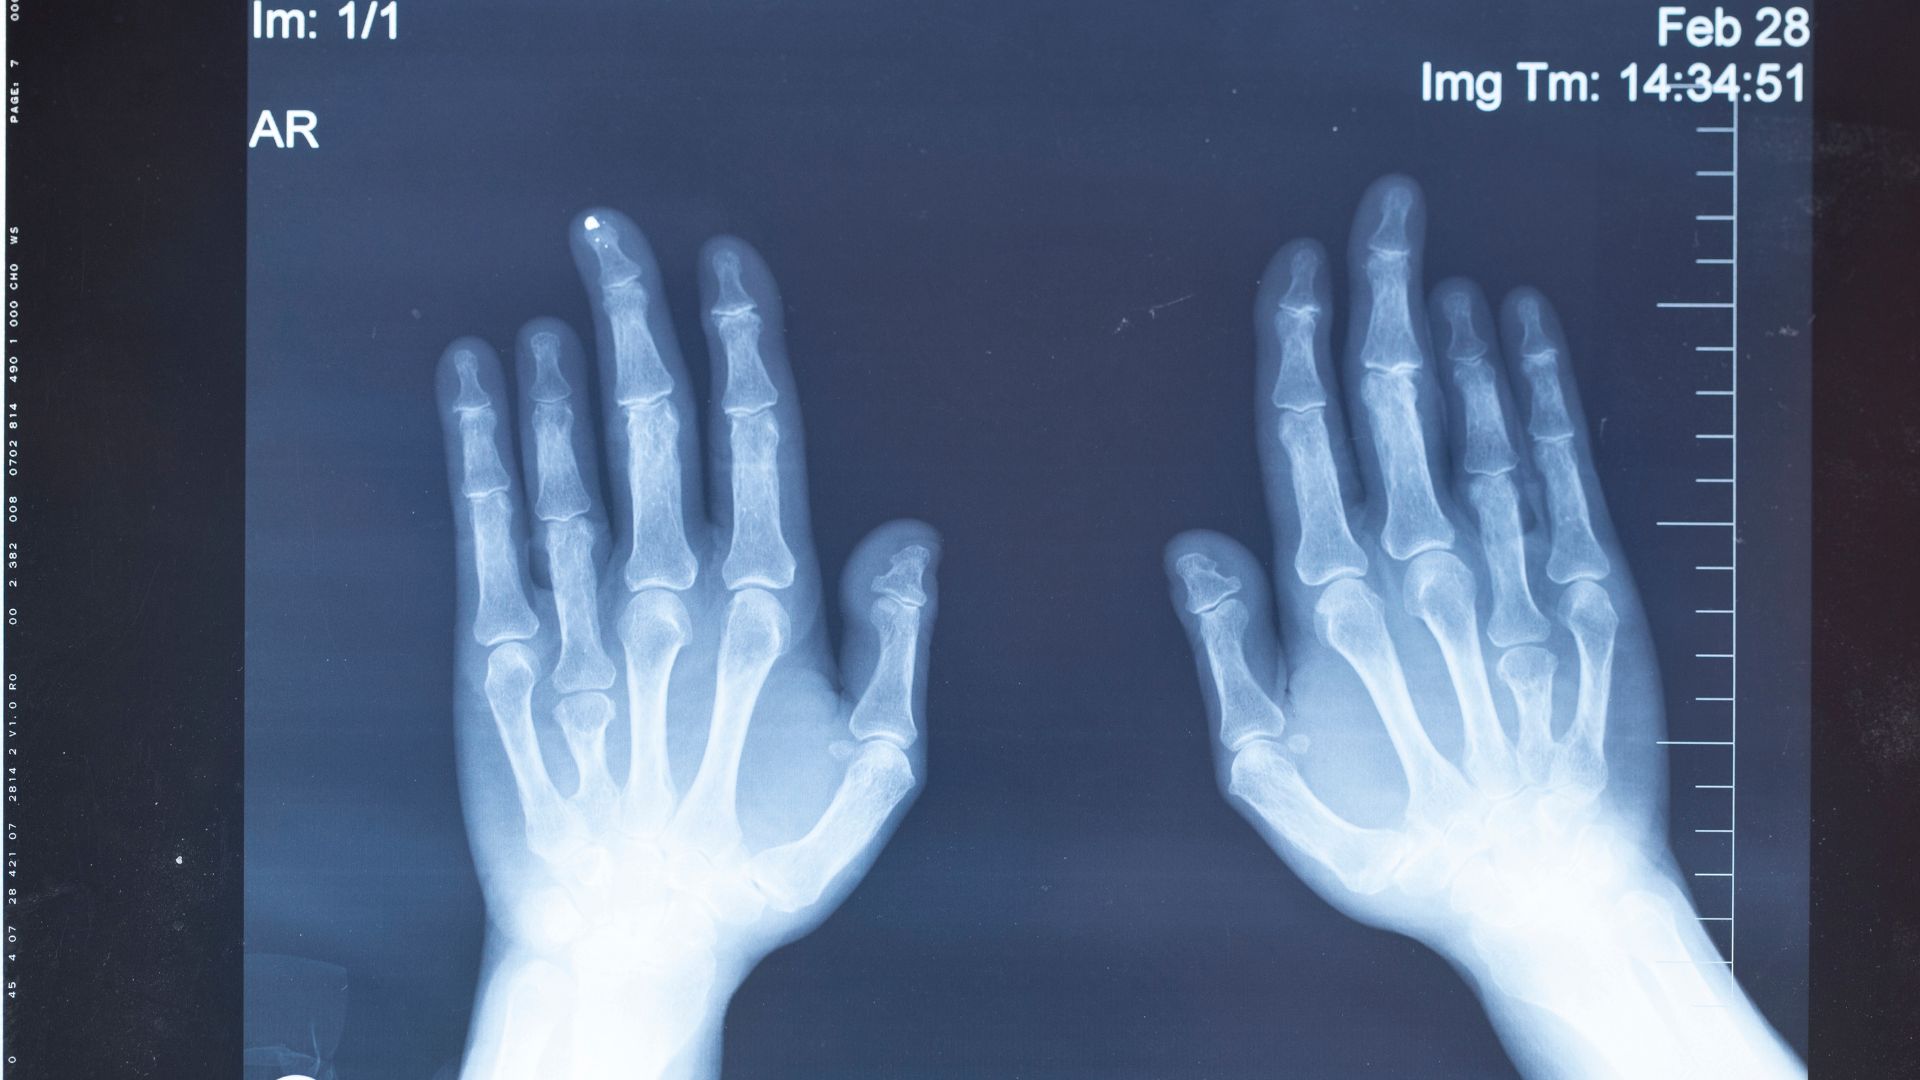

X-quang bàn tay là kỹ thuật chẩn đoán hình ảnh sử dụng tia X để tạo ra hình ảnh các xương và khớp của bàn tay, bao gồm xương cổ tay, xương bàn tay và các đốt ngón tay. Đây là phương pháp cơ bản, có giá trị cao trong đánh giá tổn thương xương bàn tay. X-quang bàn tay giúp bác sĩ quan sát rõ ràng hình dạng, vị trí, sự liên tục của các xương, từ đó hỗ trợ chẩn đoán chính xác nhiều vấn đề liên quan đến hệ xương khớp bàn tay.

Tia X đi xuyên qua bàn tay và bị hấp thụ khác nhau tùy theo mật độ của từng loại mô. Xương có mật độ cao sẽ hấp thụ tia X nhiều hơn và hiện rõ trên phim, trong khi mô mềm hấp thụ ít hơn và hiện mờ. Dựa vào sự khác biệt này, bác sĩ có thể quan sát hình dạng, vị trí, sự liên tục và mối liên hệ giữa các xương bàn tay một cách chi tiết. Nguyên lý này làm cho X-quang bàn tay trở thành công cụ hữu ích và được sử dụng rộng rãi trong chẩn đoán ban đầu.

Thông qua X-quang bàn tay, bác sĩ có thể phát hiện:

- Gãy xương bàn tay, xương ngón tay.

- Trật khớp hoặc bán trật khớp.

- Biến dạng xương sau chấn thương.

- Thoái hóa khớp bàn tay - ngón tay.

- Dị tật bẩm sinh của xương bàn tay.

- Một số dấu hiệu gợi ý bệnh lý viêm khớp mạn tính (như hẹp khe khớp, bào mòn xương).